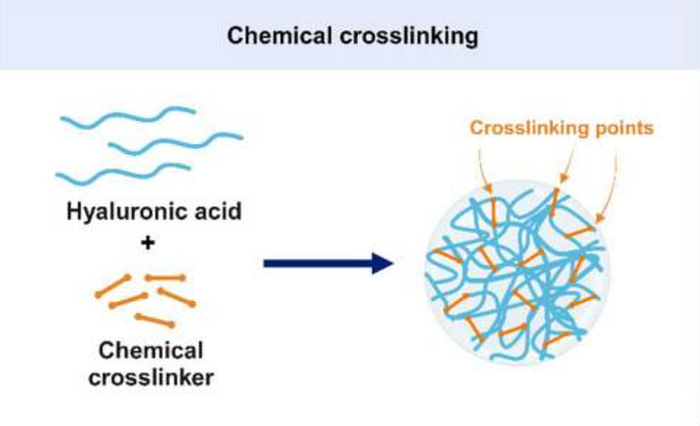

How will this product actually be made? Our nanogel will be manufactured through chemical cross-linking. Nanogels that are formed through chemical crosslinking, which creates strong covalent bonds, are stable in the body. This stability is crucial as it prevents the premature release of drugs by keeping the gel network from falling apart unexpectedly. We will use the most common method: reverse microemulsion crosslinking. In this technique, tiny water-in-oil particles called micelles serve as miniature reactors where hyaluronic acid molecules are crosslinked, allowing for precise control over the size of the resulting nanoparticles. A typical formula for these microemulsions includes water for the hyaluronic acid solution, isooctane as the oil, and sodium bis (ethylhexyl) sulfosuccinate as a surfactant. Finally, 1-heptanol will be added as a co-surfactant to increase microemulsion stability.

For the crosslinking agent, we will use 1,4-butanediol diglycidyl ether (BDDE), which has gained approval from the Food and Drug Administration (FDA). We chose BDDE because it has shown the most significant swelling response to pH changes, making it promising for various biomedical applications where biodegradability and biocompatibility are crucial. Furthermore, the swelling of nanogels in an aqueous environment allows these cargos to be released more efficiently into the surrounding environment.

Furthermore, one of the main challenges in making nanogels through chemical crosslinking is controlling their shape and size. Hyaluronic acid can turn into either a large gel network or tiny particles depending on the technique used. Our chosen method of mixing the hyaluronic acid in a water-in-oil mixture before adding the chemicals is an effective method to control the shape and size of nanogels. In this method, factors such as the ratio of water to oil, the types of surfactants (substances that reduce surface tension) used, and how vigorously the mixture is stirred can control the size of the hyaluronic particles.

Being precise with the amount of crosslinking agent is also critical. If the amount of crosslinking agent used is too small, then the physical interaction between polymer bonds breaks easily, causing the nanogel to become water soluble and could result in it dissolving too early. However, if too much crosslinking agent is used, then a high crosslinking degree causes a low swelling degree of hydrogel, which, as discussed, makes the drug release process a lot harder.

In a study testing chemical crosslinking using BDDE, high crosslinking yields of over 90% were confirmed for all samples except when a 1:10 hyaluronic acid to BDDE molecular weight ratio was used. In these cases, the excess BDDE caused problems due to a large amount of unreacted BDDE, which limits the effectiveness (reduced solubility, improved elasticity, and enhanced mechanical strength and stability) of using high concentrations of BDDE in making hyaluronic acid nanogels. It was also found that using a low amount of BDDE significantly impacted the size of the nanogels, regardless of the HA’s molecular weight. Nanogels made with just 0.2 equivalents of BDDE had much larger particle sizes compared to those made with higher ratios of hyaluronic acid to BDDE (1:1 and 1:10). These low-crosslinked nanogels (1:0.2 hyaluronic acid:BDDE) also displayed better swelling properties, meaning they could absorb more water and expand more when the pH changed or when transitioning from dry to wet states. Thus, we now encounter a situation where we need to evaluate the trade-offs of using a high amount of BDDE versus a low amount.